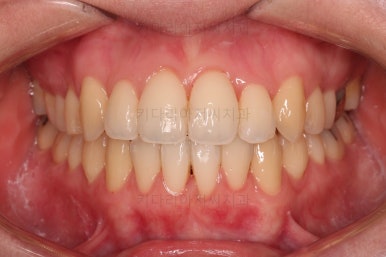

1년 2개월이라는 비교적 짧은 기간안에 원하시는 부분을 깔끔하게 개선했습니다.

전후 비교해 볼게요.

입이 나오거나 뻐뜨러지는 느낌 전혀 없죠?